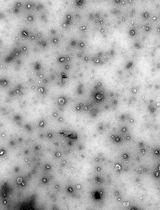

Protocol for the Isolation and Analysis of Extracellular Vesicles From Peripheral Blood: Red Cell, Endothelial, and Platelet-Derived Extracellular Vesicles

外周血中细胞外囊泡的分离与分析方法:红细胞、内皮细胞及血小板来源的细胞外囊泡